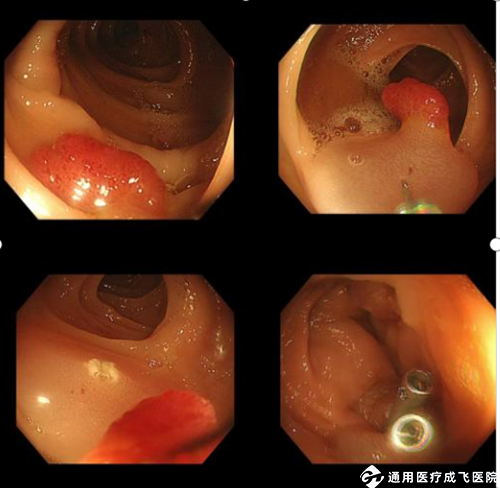

相比起小息肉的切除办法,内镜医生需要根据病变因素,息肉的形态、位置等等进行综合评估,再进一步选择治疗方案,EMR与ESD操作步骤更复杂,需要更精细的手术技巧和更长的时间来进行摘除,无法在常规的胃肠镜检查中完成,并且较大息肉摘除完会存在一定的出血、穿孔、感染等风险,而最常见的并发症就是出血,对于术中出血可以立即处理,但一部分患者可能发生迟发性出血(通常发生在术后2-7天),考虑到患者的安全以及并发症的出现,所以建议患者住院切除,必要时可能需要再次内镜下止血。不同的切除方式:

图3 :EMR(内镜下黏膜切除术)

图4:ESD(内镜黏膜下剥离术)